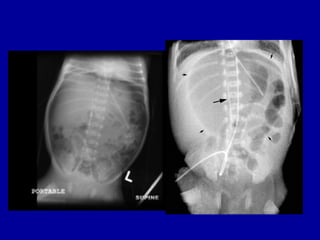

Blood in stool at 4 am, axr 6 am

Blood in stool AXR 10. 30 am,

Blood in stool AXR 14.24 pm,